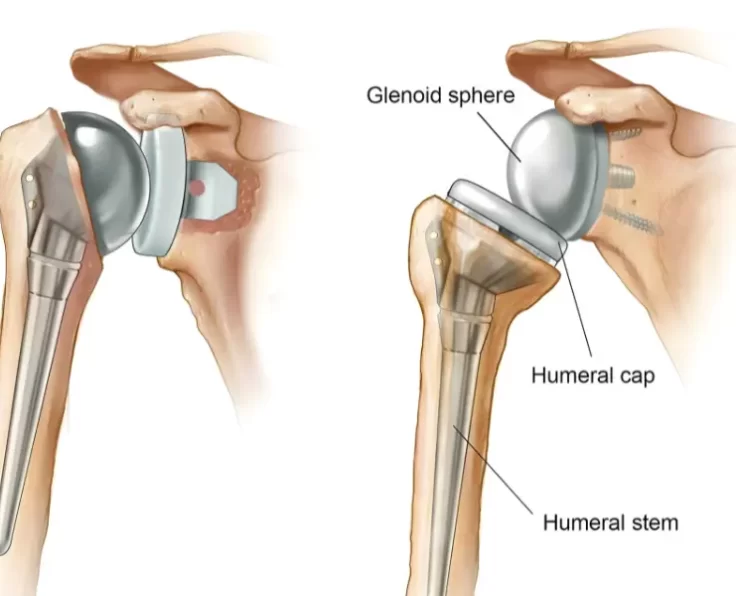

Short Stem Shoulder Replacement

The humeral implant is maintained in place by a "stem" that runs down the centre of the humerus in a typical shoulder replacement design (arm…

Resurfacing of Shoulder

The humerus (arm bone, which is the ball) and the glenoid (socket) are the two main components of your shoulder (socket).

Total Shoulder Replacement

Prime Shoulder Care is the most preferred clinic for Shoulder Replacement in Chennai.

Reverse Shoulder Replacement

This is a therapeutic option for shoulder arthritis that is also accompanied by rotator cuff problems.